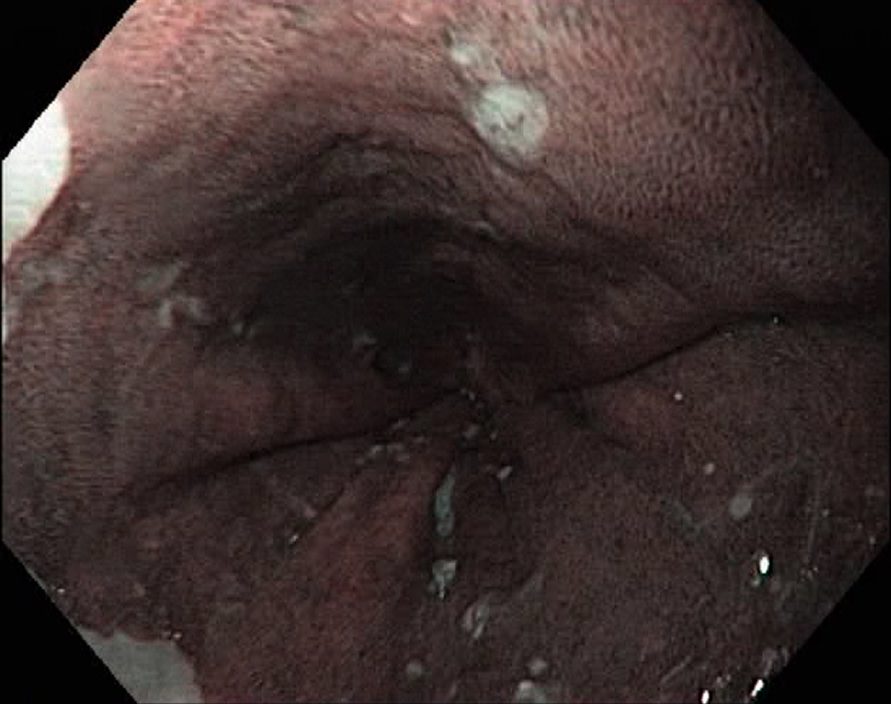

Barrets Oesophagus (NBI, Narrow Band Imaging)